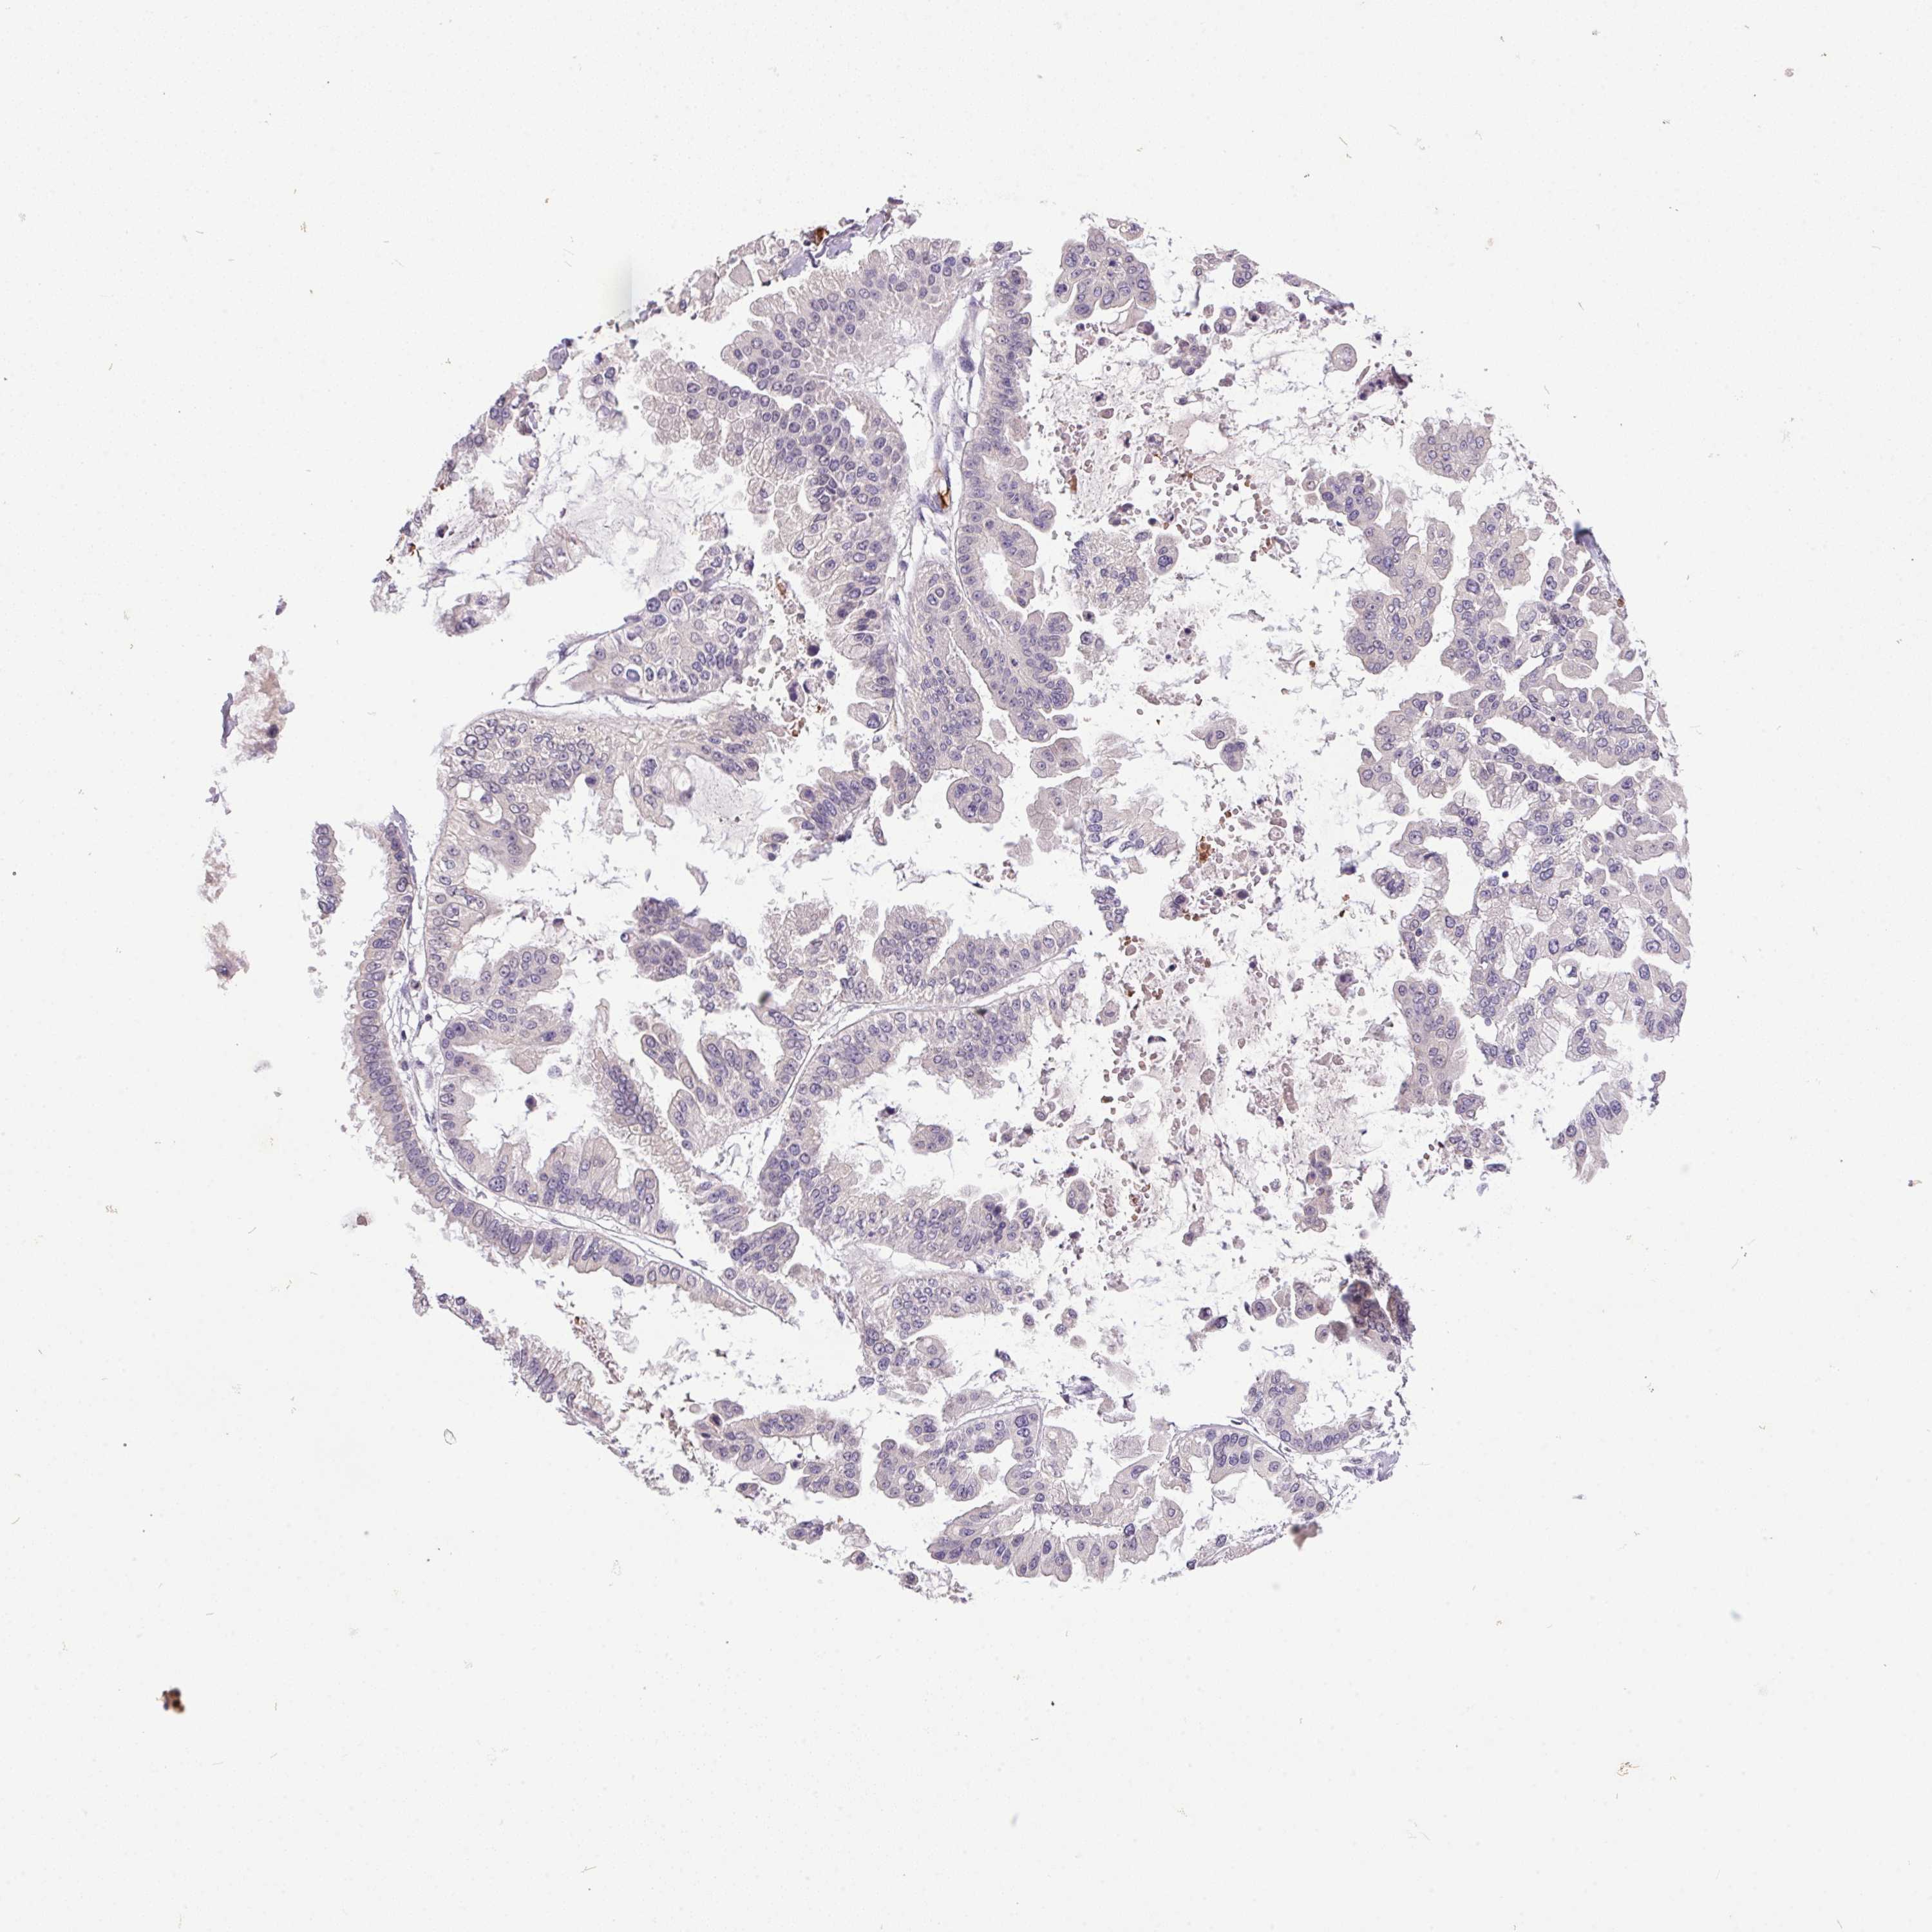

OVARIAN CANCER - Protein expressioni

A mouse-over function shows sample information and annotation data. Click on an image to view it in a full screen mode. Samples can be filtered based on level of antibody staining by selecting one or several of the following categories: high, medium, low and not detected. The assay and annotation is described here.

Note that samples used for immunohistochemistry by the Human Protein Atlas do not correspond to samples in the TCGA dataset.

Antibody stainingi

Antibody staining in the annotated cell types in the current human tissue is reported as not detected, low, medium, or high, based on conventional immunohistochemistry profiling in selected tissues. This score is based on the combination of the staining intensity and fraction of stained cells.

Each image is clickable and will lead to virtual microscopy that enables deeper exploration of all samples and also displays staining intensity scores, fraction scores and subcellular localization as well as patient and tissue information for each sample.

Antibody HPA038226

Antibody HPA058226

Cystadenocarcinoma, serous, NOS

Carcinoma, endometroid

Cystadenocarcinoma, mucinous, NOS

Carcinoma, NOS